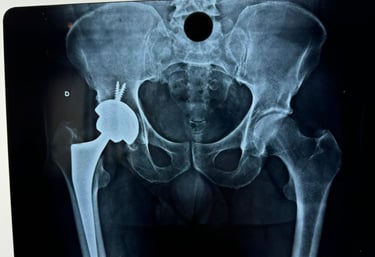

As patologias do quadril podem estar relacionadas a traumatismos prévios,  mas também podem ser secundárias a doenças prévias ou idiopáticas. Algumas das principais patologias  relacionadas ao quadril são: Fraturas da cabeça do fêmur e bacia, Coxartrose, Bursite Trocantérica, Impacto Femoroacetabular, Osteonecrose do Quadril, Síndrome do Piriforme, Tendinite do Quadril.

Tratamento de patologias do Quadril

• Cirurgia de Prótese de Quadril.